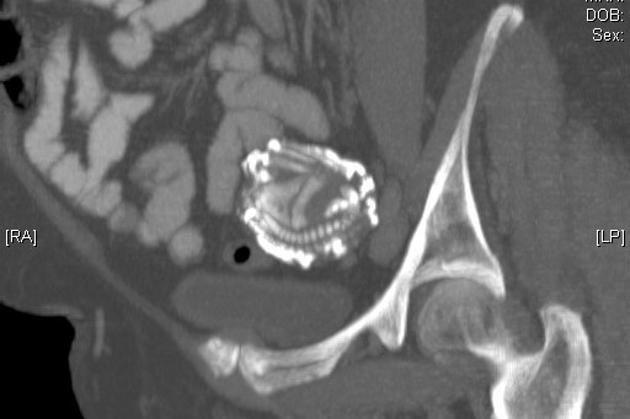

Giáo sư Taibi tiến hành siêu âm và nhận thấy một "vật thể lạ khá lớn" không xác định được. Ông giới thiệu Zahra đến gặp một chuyên gia chụp X quang. Cuối cùng, kết quả chụp MRI xác nhận rằng nó thực sự là đứa con chưa chào đời của bà.

Hình ảnh em bé nằm trong bụng bà Zahra.

Bà Zahra đã mang thai ngoài tử cung, khi bào thai ngày càng to dần, nó làm vỡ ống dẫn trứng, tiếp tục phát triển trong ổ bụng và sống sót bằng cách gắn nhau của nó vào các cơ quan nội tạng trong bụng bà Zahra.

Thai nhi đã hóa đá trong bụng bà Zahra.

Khi các bác sĩ thực hiện phẫu thuật, họ phát hiện ra bào thai đã bị vôi hóa, là một khối cục rất rắn và đặc. Về cơ bản đó là một "em bé đá", đã gắn chặt với thành bụng và các bộ phận quan trọng trong người bà Zahra. Sau 4 tiếng phẫu thuật, các bác sĩ đã lấy ra bào thai thành công. Em bé nặng 3,2kg và dài 42cm.